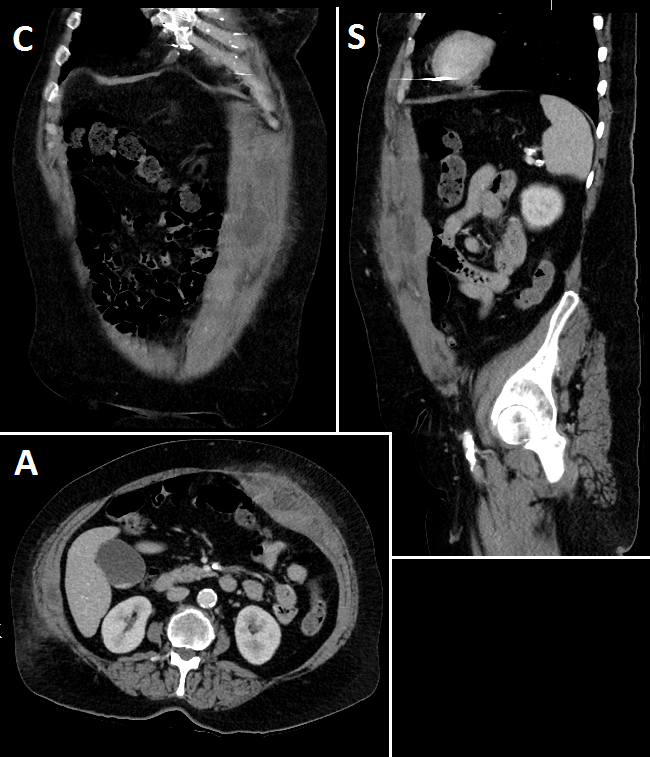

Standard adult abdominal phantom with liver, kidneys, spleen, and bowel